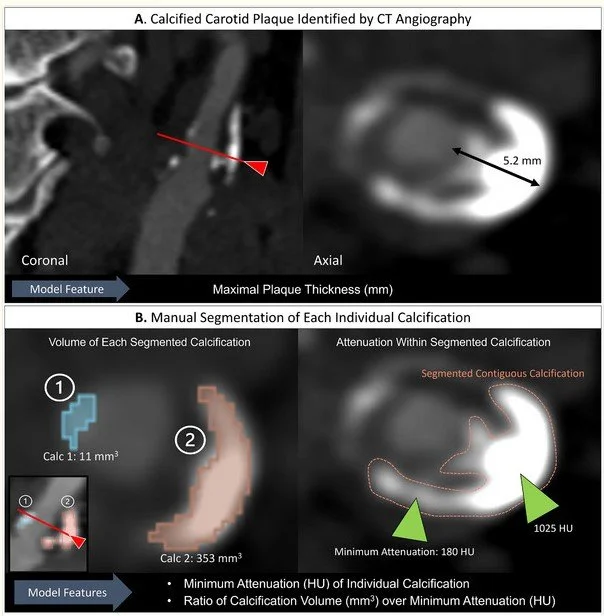

Explainable Machine‐Learning Model to Classify Culprit Calcified Carotid Plaque in Embolic Stroke of Undetermined Source (Jan 2026)

We applied an explainable ML approach, using noncalcified plaque components and calcification features to classify plaques as culprit or nonculprit in an ESUS cohort.

Association of Carotid Plaque Calcification Attenuation With Intraplaque Hemorrhage Volume: 3D-Segmentation Analysis (Jul 2025)

We investigate the association between morphologic and attenuation features of plaque calcifications and intraplaque hemorrhage to show that attenuation influences high risk features of carotid plaque.